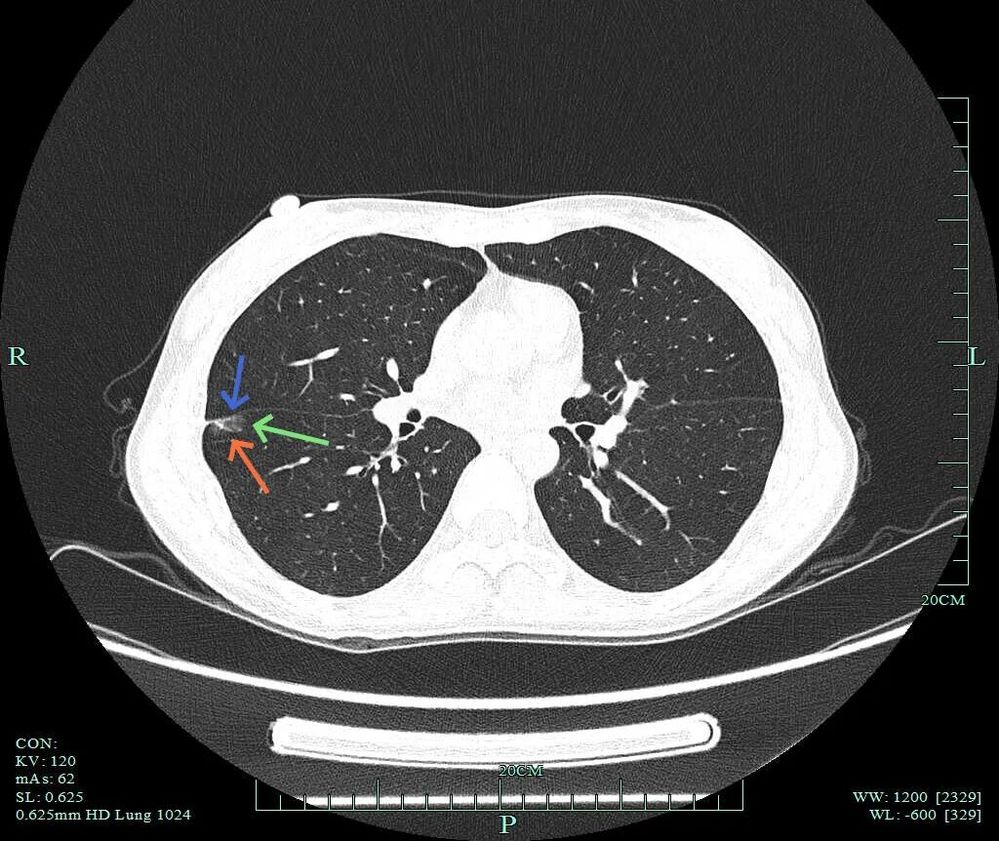

上叶病灶B也是磨玻璃密度的,轮廓与边界清。

上叶病灶D邻近病灶B,但太微小,也很淡。

下叶病灶C也是磨玻璃密度,但位置较深,在前基底段与内基底段交界附近,考虑不典型增生或原位癌可能性大,尤其是前者。